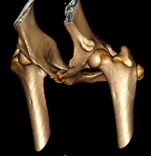

Abb 2 Huefte DysplastischAls „Hüftgelenkdysplasie“ wird eine Fehlbildung der gelenkbildenden Strukturen bezeichnet. Die knöchernen Strukturen passen nicht zusammen, die Weichteile (insbesondere die Kapsel) sorgen nicht für einen straffen Zusammenhalt („Laxizität“), oder es liegt (wie in den meisten Fällen) eine Kombination aus beiden Faktoren vor. Egal in welcher Form die Hüftgelenkdysplasie auftritt, sie führt unweigerlich zu einer Arthrose des Gelenkes. Der Grad der Arthrose kann sehr unterschiedlich sein und hängt indirekt auch mit dem Grad der Fehlbildung des Gelenkes zusammen.

Die Abbildung zeigt die Röntgenaufnahme des Beckens eines Hundes mit schwerer HD. Die Arthrose ist jedoch zum Zeitpunkt der Aufnahme gering ausgeprägt.